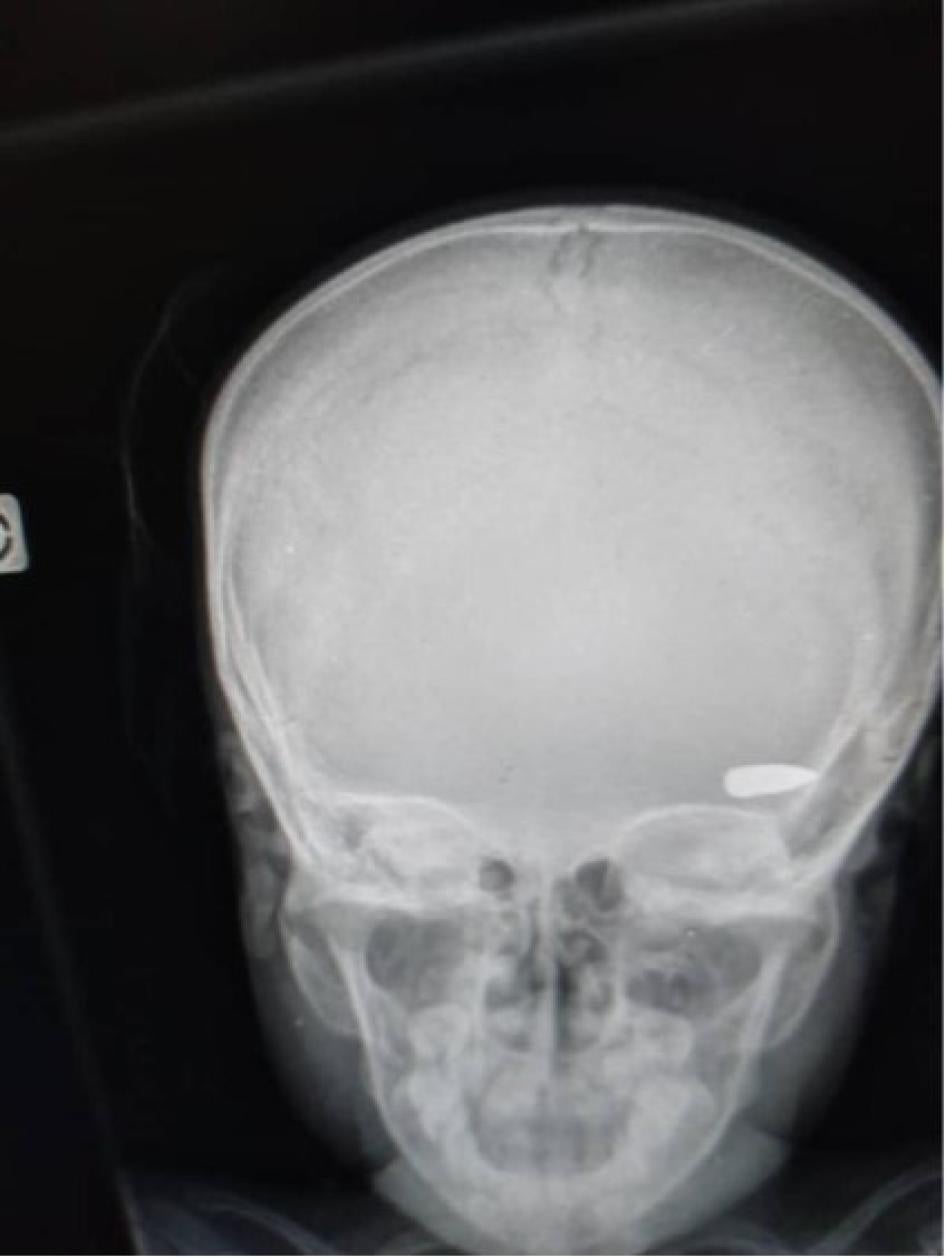

At least 45 victims died from gunshot wounds, while others were attacked with machetes, and some were burned alive inside their homes. Most of those shot were hit in the head, chest, or back, and appear to have been targeted. Two were apparently victims of stray bullets while they were inside or just outside their homes, and one victim was shot while fleeing during clashes between different criminal groups. In a few cases, family members were able to recover the bodies of their loved ones for burial. Most bodies, however, were burned in the streets or taken away by the criminal groups.[41]

Human Rights Watch documented 35 killings in this area, including of 6 children, and 17 cases of sexual violence. In addition, five people injured by gunshot at Carrefour la Mort were interviewed while being treated at a hospital in Port-au-Prince.